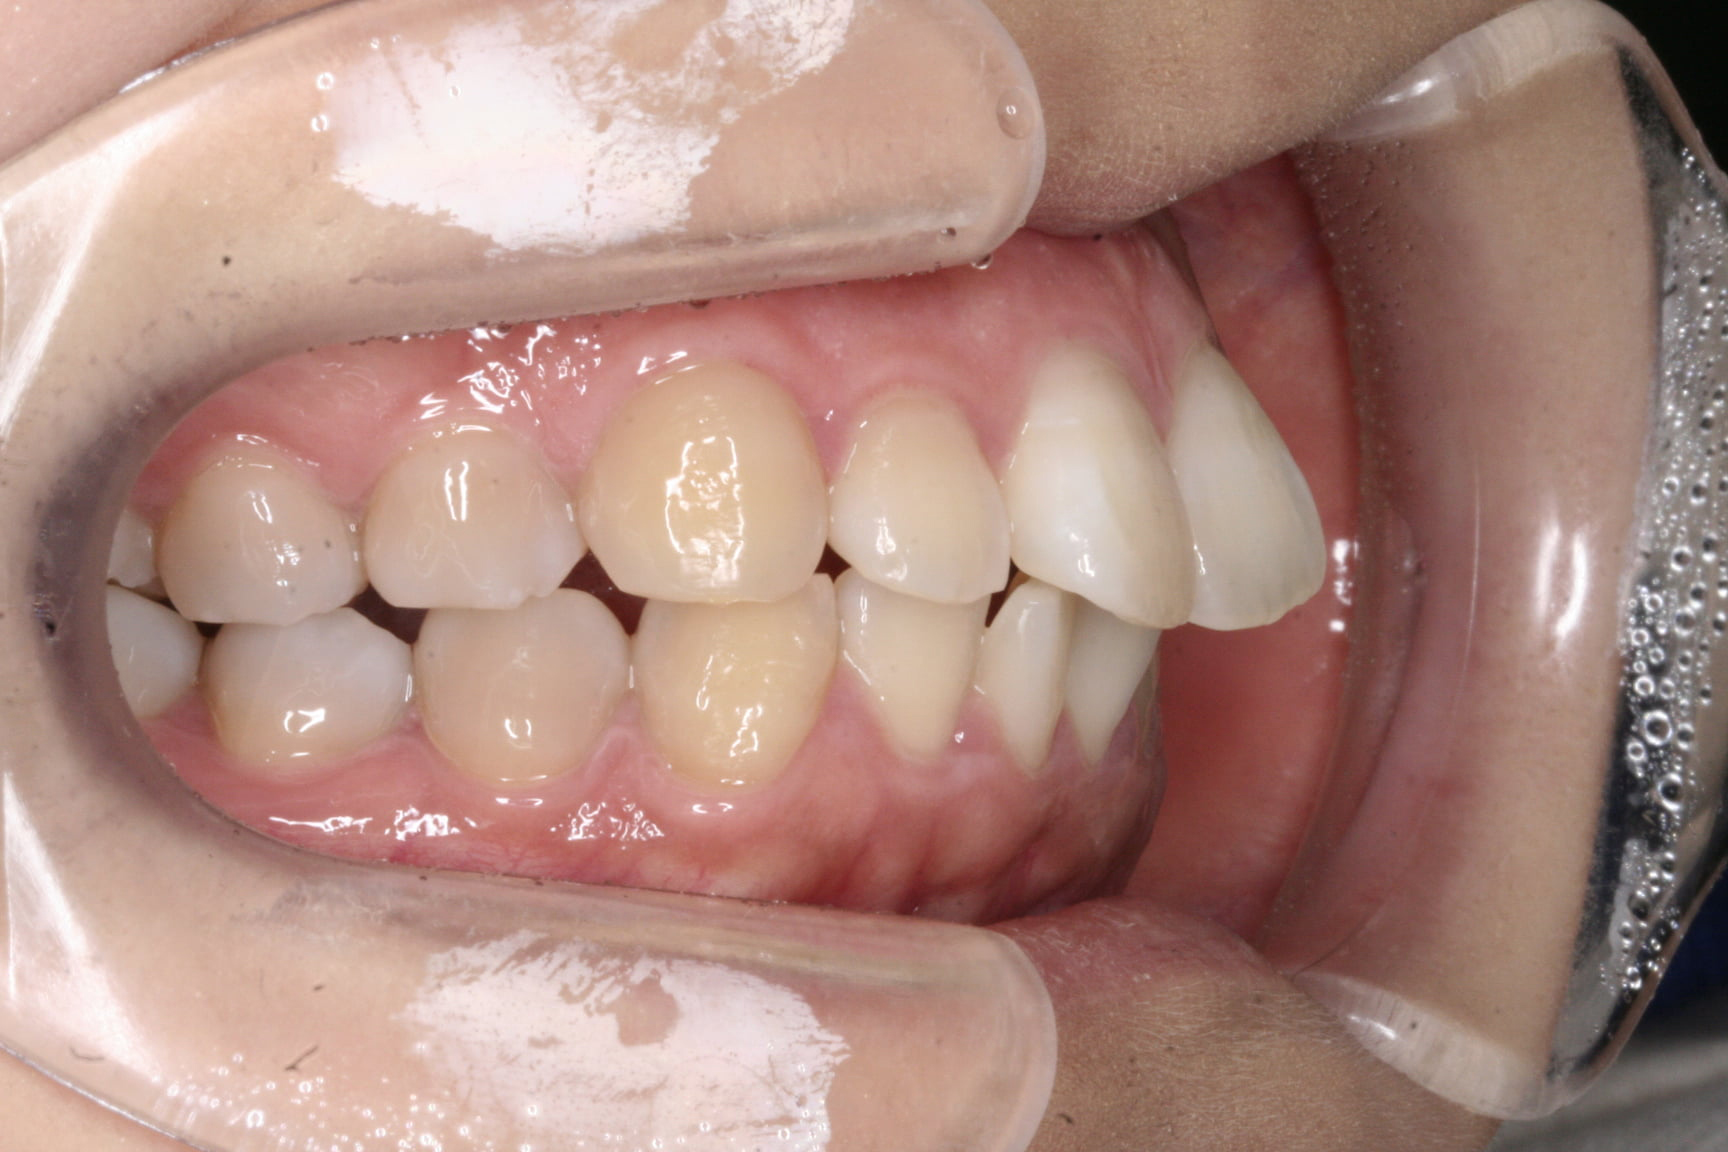

出っ歯を治したい

年齢層 30代

性別 女性

主訴 【主訴】出っ歯を治したい 【診断・症状】上下凸凹、口元が出てる

治療費用 検査・診断:38,500-/裏側矯正治療:1,397,000-(※全て税込)

治療期間 約2年9か月(36回)

抜歯 抜歯:有(上4,4)

矯正の装置 裏側矯正(舌側矯正)

副作用、リスク 歯肉退縮,歯根吸収,疼痛,咬合の違和感,装置の違和感,虫歯,歯肉炎

case21_出っ歯_before

Before

case21_出っ歯_after

After